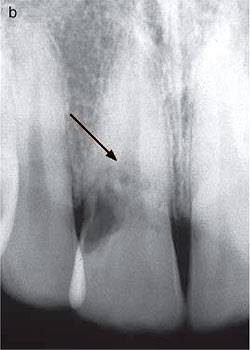

แสดงรอยโรค Class 4 ซึ่งเป็นระยะที่แรงสุด รอยโรคลงไปเกิน Coronal 3rd of root ลูกศรแสดงขอบเขตของ pulp ที่เป็น radiopaque line

ภาพตัด section ของรากฟัน จะเห็นผนังที่หุ้ม pulp เพื่อแยกจากขอบเขตของรอยโรค ชัดมากๆ